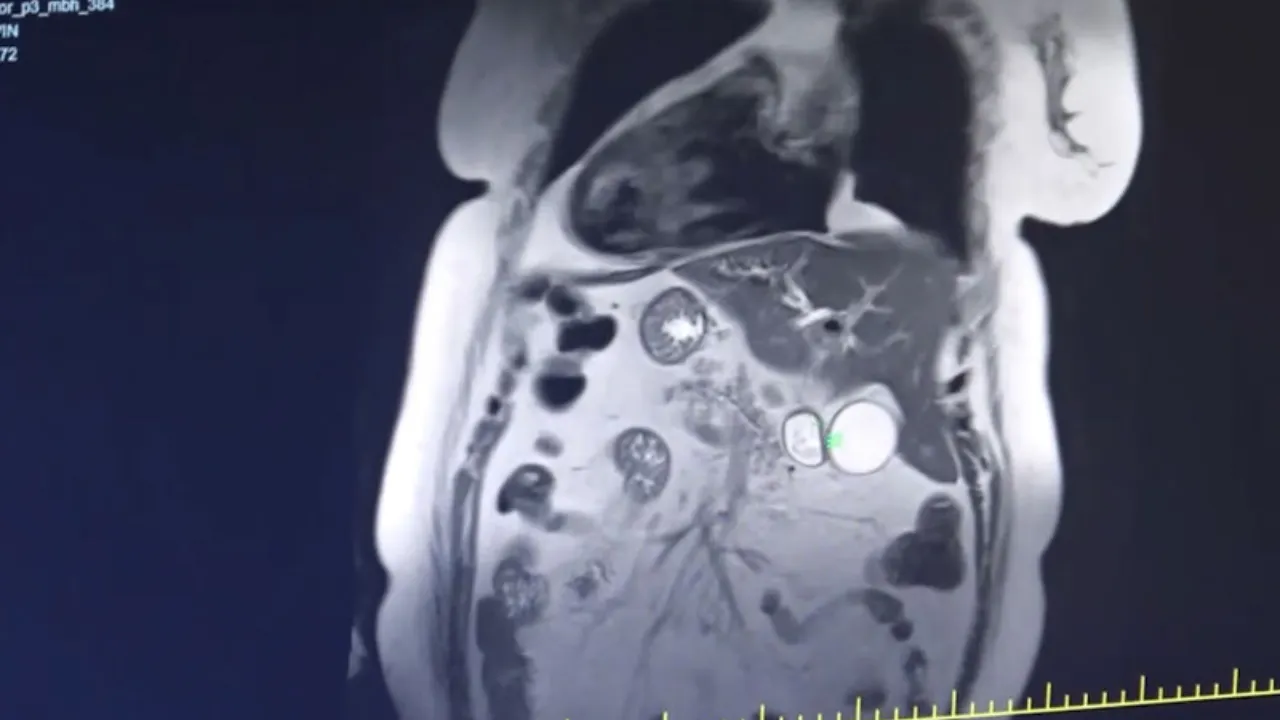

Son olarak Gaziantep Şehir Hastanesi'ne başvuran Evin Aslan'ın hastanede yapılan tetkikler sonucunda iç organlarının tamamının ters tarafta olduğu anlaşıldı. Kalp, mide, dalağı, göğüs ve karın bölgesinin sağında, karaciğer ve safra kesesinin ise solda olduğunu öğrenen Aslan, hayatının şokunu yaşadı.

İç organlarının tamamının ters tarafta olduğunu öğrenen Aslan, safra kanalındaki taşlar nedeniyle çektiği ağrılardan kurtulmak için ameliyat olmaya karar verdi. Aslan'ın yıllarca çektiği tüm acılar ve ağrılar, Gaziantep Şehir Hastanesi'nde yapılan başarılı ameliyat sonucu son buldu. Meslek hayatında ilk kez böyle bir durum ile karşılaştığını belirten Gastroenteroloji Uzmanı Dr. Ahmet Akbay, "Hastamız karın ağrısı şikayetiyle hastanemize başvurdu. Çekmiş olduğumuz MR'da karın iç organlarının tam tersi yerleşmiş olduğunu gördük. Bu duruma ‘situs inversus totalis' denilmektedir. Sağda olması gereken karaciğer ve safra kesesi sol tarafa ve solda olması gereken kalp ise sağ tarafa yerleşmişti. Bu hastamızda safra kanalında taş olup akut pankreatitleri geçirmekteydi. Hastamızın safra kanalındaki taşlarını ileri endoskopik yöntem olan RCP işlemiyle başarılı bir şekilde yaptık" dedi.

Tıp literatüründe çok fazla gözükmeyen bir olayla karşılaştıklarını belirten Akbay, "Bu durum dünyada ve Türkiye'de çok nadir görülen bir durumdur. Hem organların ters tarafta olması aynı zamanda safra kanalında taş ve pankreatitleri geçirmesi çok nadir görülen bir durumdur. Dolayısıyla ileri endoskopik yöntem olan RCP işlemi içinde hastanın tam ters pozisyonda, odanın dizaynını ona göre ayarladık, işlem oldukça zor olmasına rağmen başarılı bir şekilde işlemimizi yaptık, hastamız sağlığına kavuştu" şeklinde konuştu.